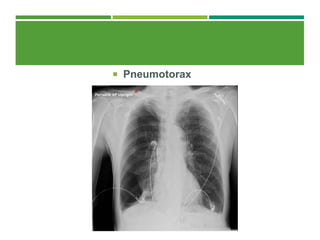

 O pneumotórax pós-operatório pode acompanhar a

inserção de cateter na veia subclávia ou a ventilação

por pressão positiva, mas, algumas vezes, surge após

uma cirurgia durante a qual a pleura foi atingida

 Em geral, o pneumotórax deve ser tratado com

drenagem pleural, dependendo de seu tamanho e

etiologia.

 Pneumotorax